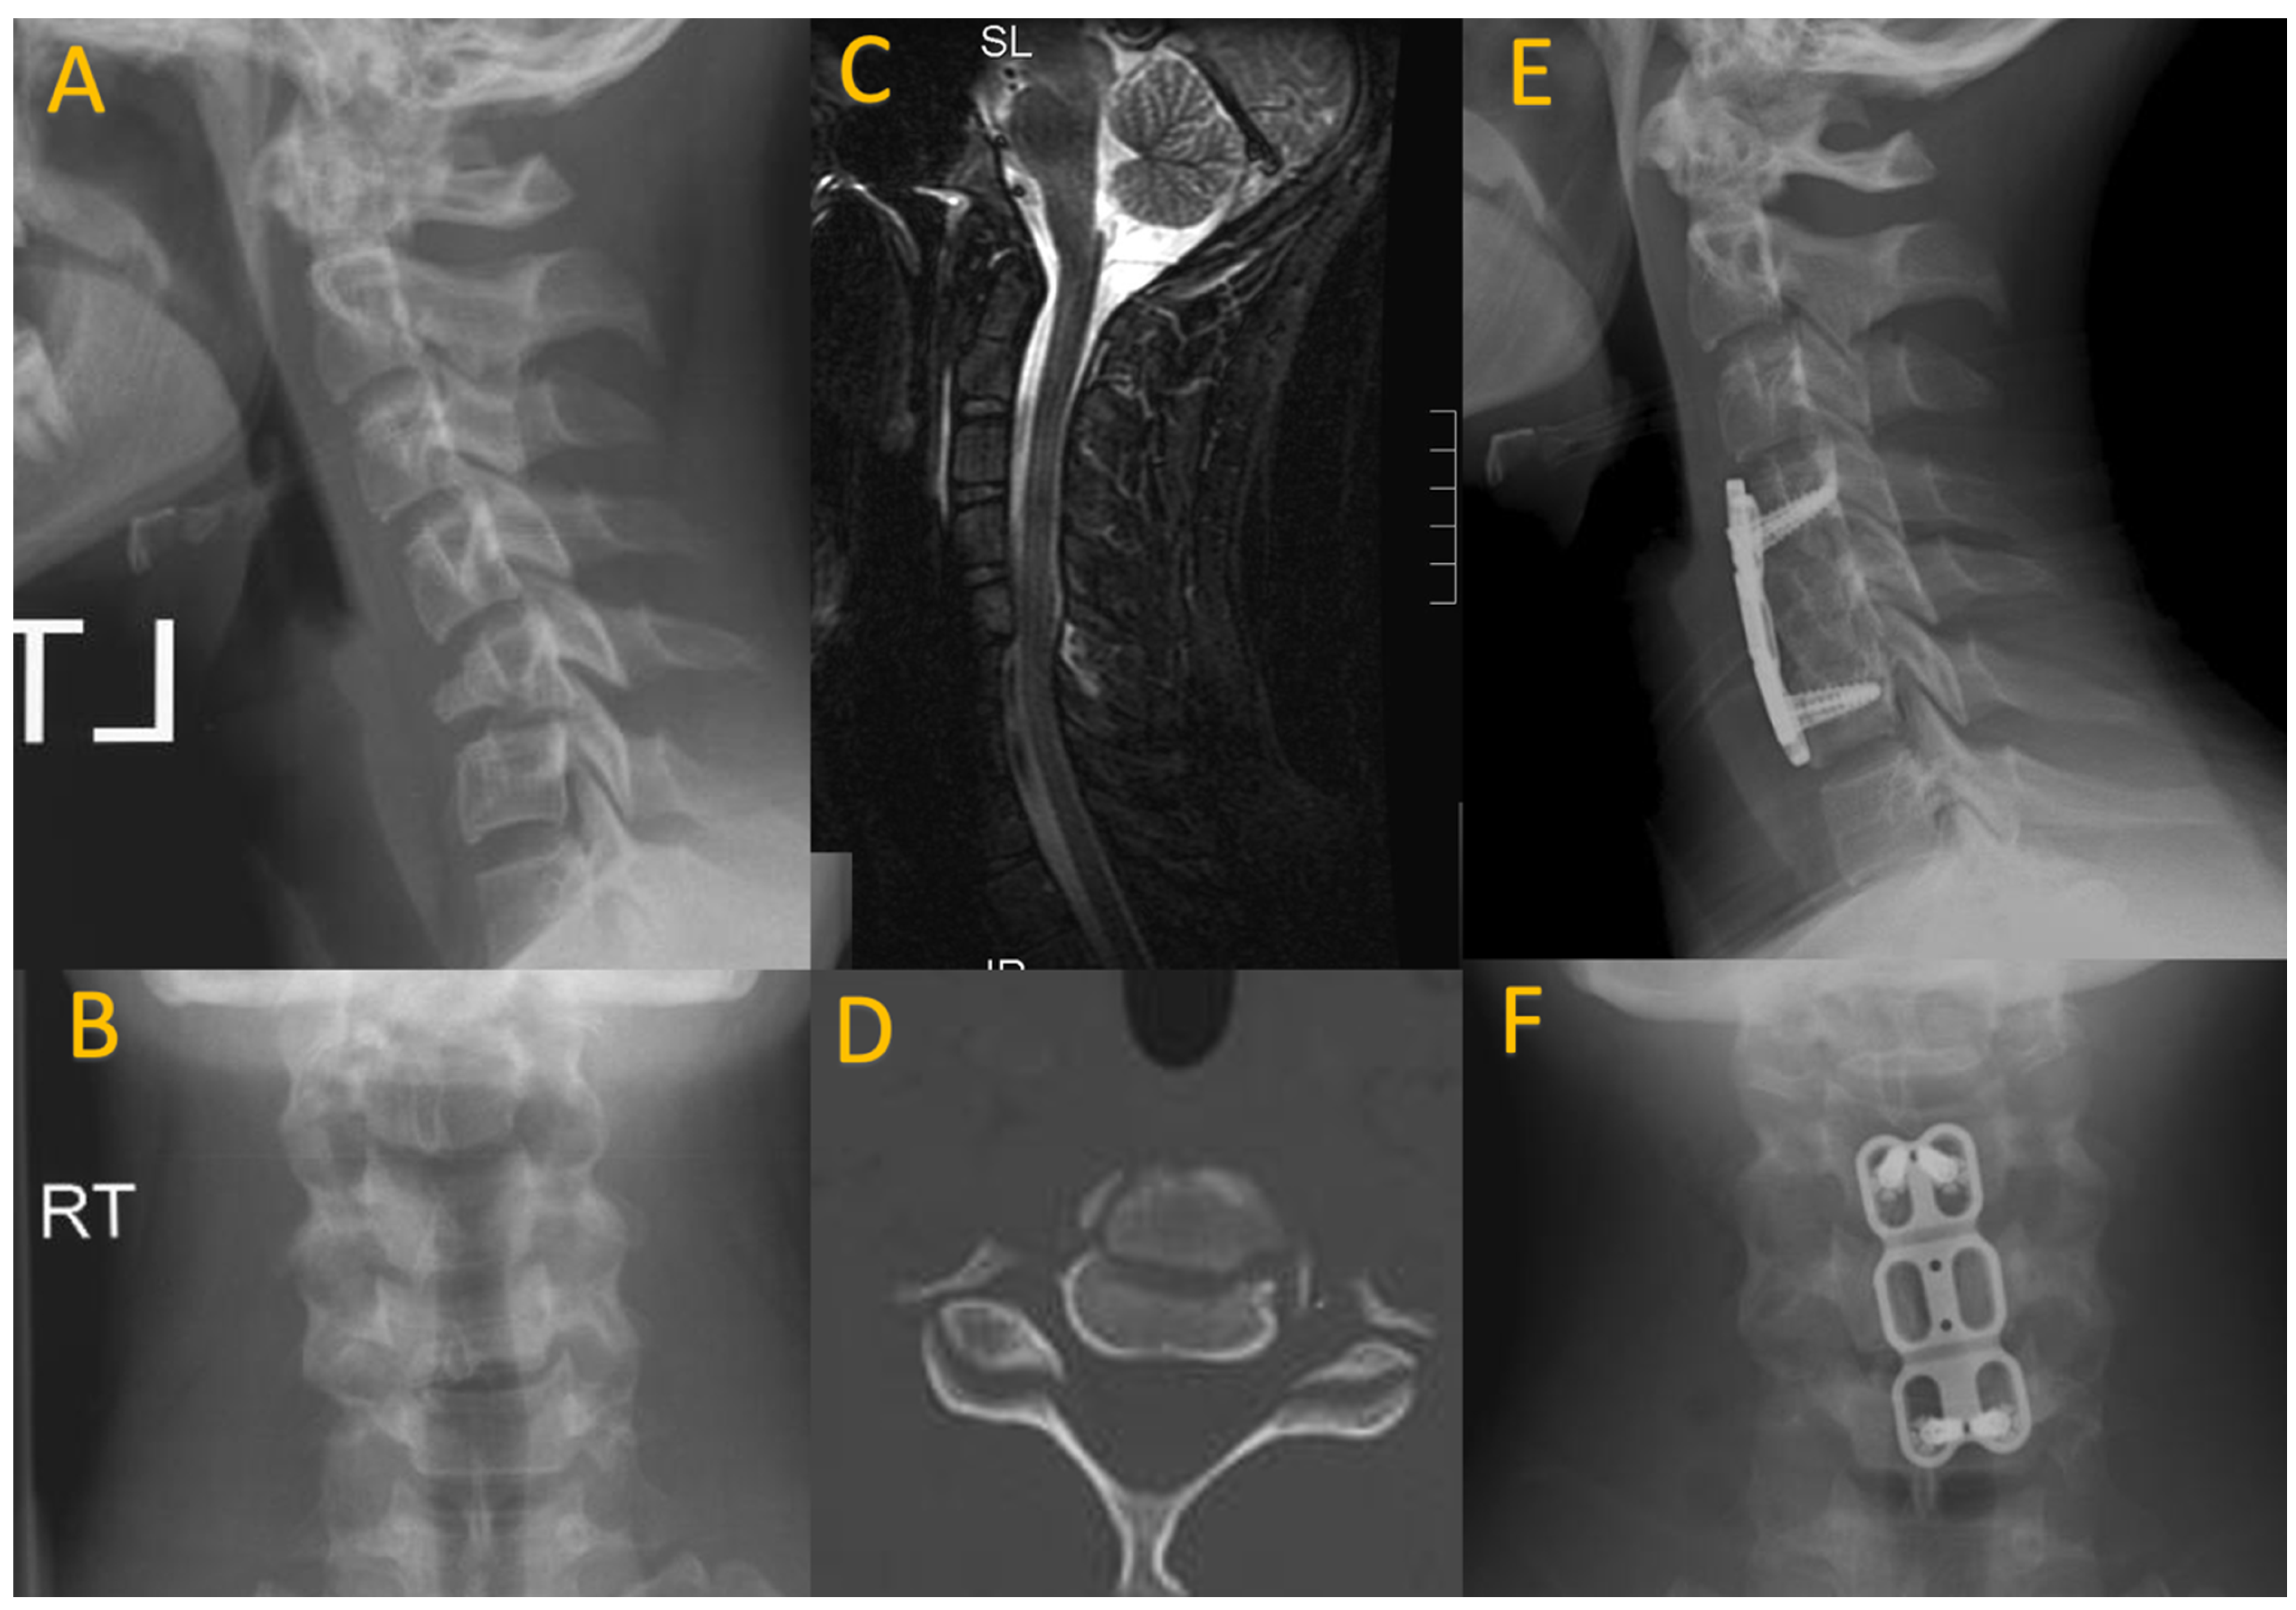

Odontoid fractures, although rare in pediatric patients, can occur at the dentocentral synchondrosis, generally in younger patients (as the dentocentral synchondrosis fully fuses between 9 and 10 years) [22]. Anterior angulation or displacement of the odontoid process can be seen on lateral X-rays. These fractures are most often treated with external immobilization [23]. Os odontoideum involves the superior portion of the odontoid process being separate from the rest, often considered to be congenital, but increasing evidence suggests it is associated with chronic nonunion or an odontoid fracture [23,24]. Os odontoideum may be especially relevant in pediatric patients with a remote history of TBI, and often requires C1–2 instrumentation and fusion to avoid further neurologic complications (Figure 2) [24].

Figure 2.

A 16-year-old boxer who presented after developing transient paraplegia while boxing. CT imaging revealed os odontoideum (A,B) with hypermobility on flexion and extension cervical X-rays (C,D). He underwent posterior C1–2 fusion with instrumentation, wiring, and allograft (E,F).